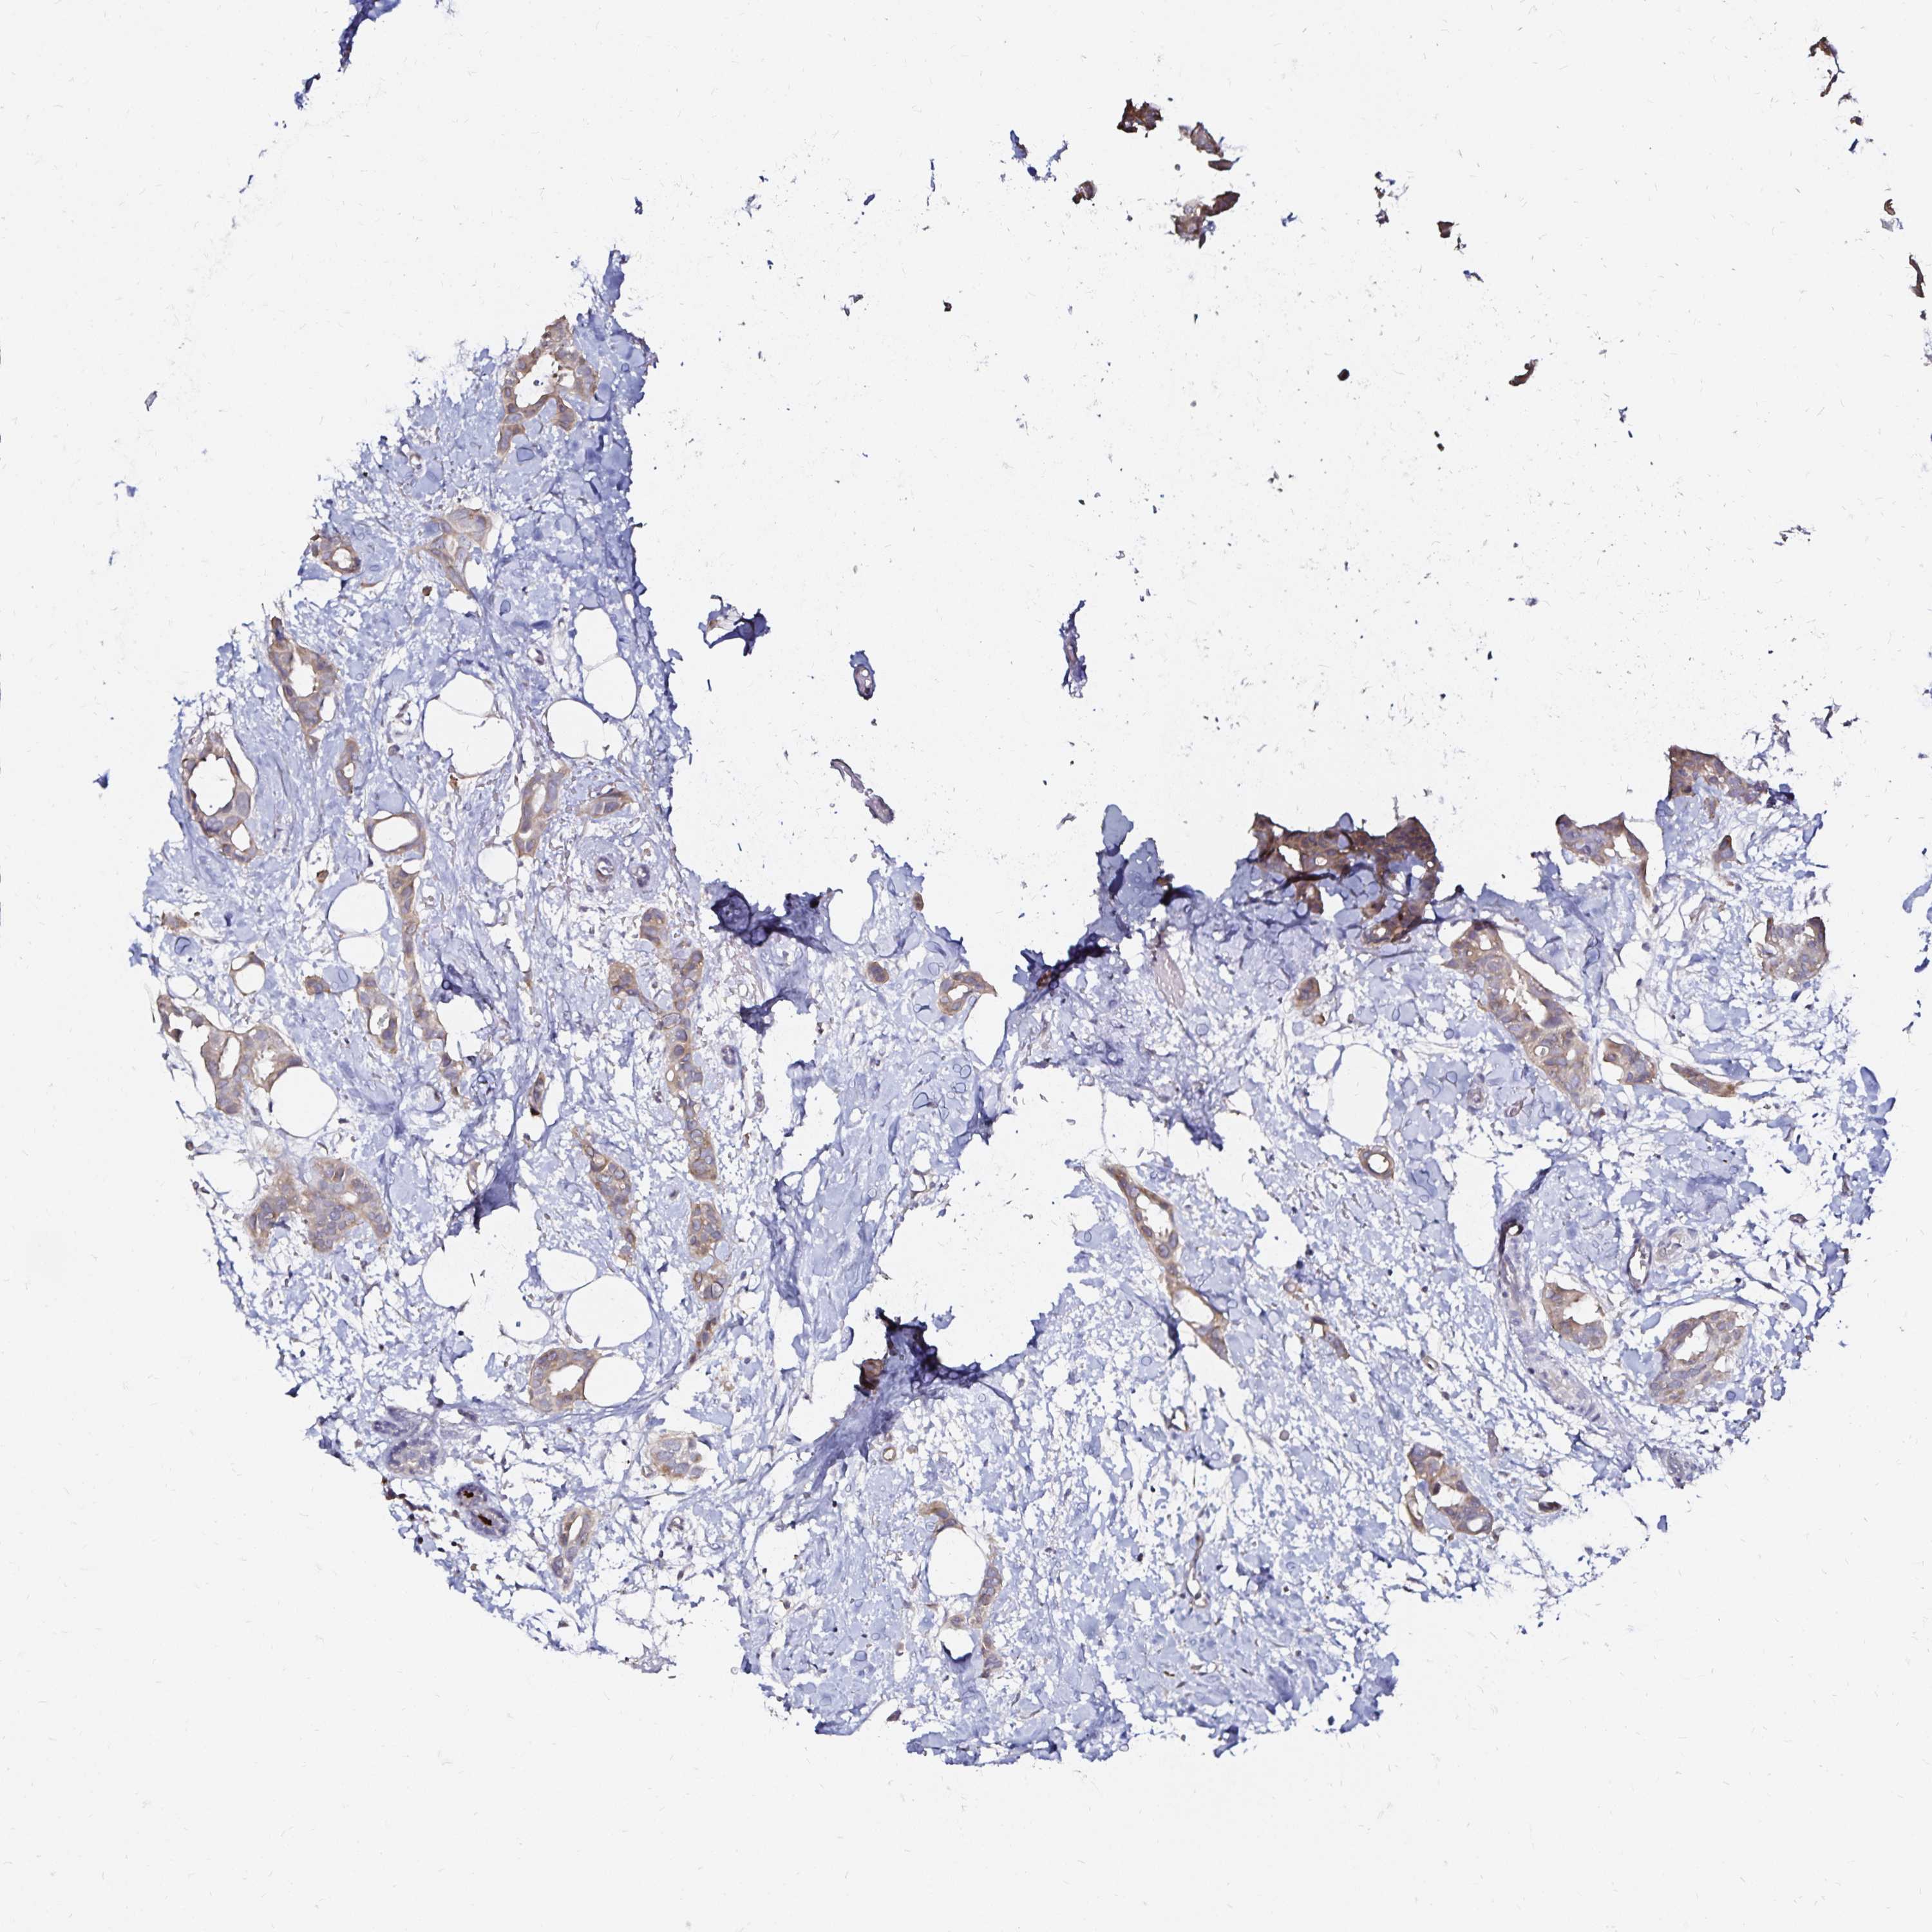

CANCER BREAST CANCER Show tissue menu

BRCA TCGA BRCA VALIDATION PROTEIN EXPRESSION

Breast cancer

Human cancer